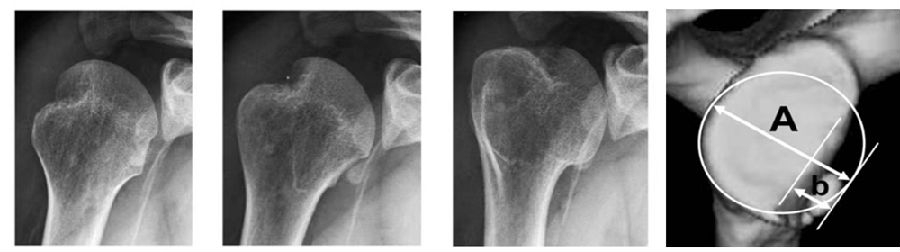

当手臂上举时,肩胛盂与肱骨头的接触区域会从肱骨头的中下部向外上部分转移,这个相互的接触区域就被称为肩胛盂轨迹。接触区域的内侧缘到肩袖止点的内侧缘的距离约为84%肩胛盂的宽度。

图12

当没有肩胛盂骨缺损时,肩胛盂轨迹的宽度占了肩胛盂宽度的84%。当有肩胛盂前缘骨缺损时,应该从这84%的长度中减去骨缺损的宽度,这样才能够获得一个真正的肩胛盂轨迹的宽度。

上图显示接触区域的内侧缘到肩袖止点的内侧缘的距离约为83%肩胛盂的宽度。A1-B1是肩胛盂的长轴,C-D是肩胛盂的宽度,E-D是肩胛盂轨迹,为83%肩胛盂的宽度。B图为盂肱关节在外展外旋位的对合关系,肱骨头和肩胛盂接触区域内侧边缘(M)到肩袖足印区的内侧边缘(F)的距离,是肩胛盂宽度的83%±14%。(肩胛盂轨迹=F-M=83%肩胛盂的宽度)。

图16